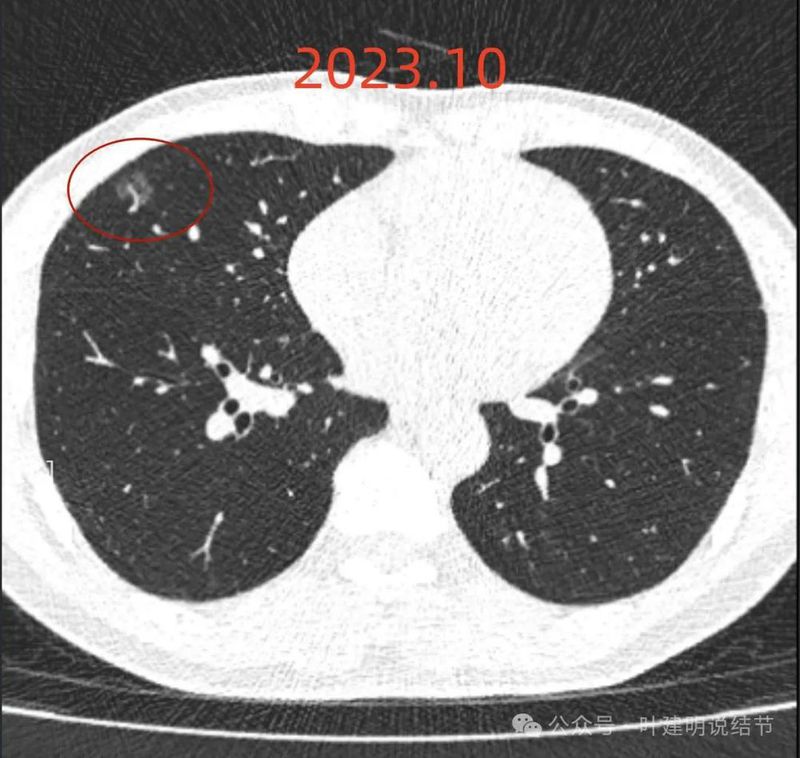

2023年10月时病灶又有进展,表面有细毛刺、灶内血管明显异常增粗,中间仍有小的空泡征,整体轮廓与边界清,大小也有所增大。磨玻璃部分的密度也较之前有所增加。

病灶出现,磨玻璃密度,轮廓较清,有微血管进入。

分叶征明显,灶内似有细支气管扩张,表面不平。

胸膜间隙征存在;血管进入与异常增粗,边缘细毛刺,整体轮廓与边界清。

中间仍有空腔征,表面细毛刺,整体轮廓清。

囊壁密度不均,有少许偏实性成分,边缘细毛刺,有小血管进入。

毛刺征明显且典型,血管进入并增粗,邻近胸膜似略有牵拉影响。

边缘部分也密度欠均匀,相应胸膜稍有牵拉影响。

表面不平,轮廓清,有分叶,有胸膜牵拉。

边缘也是磨玻璃成分,边界与轮廓清楚。